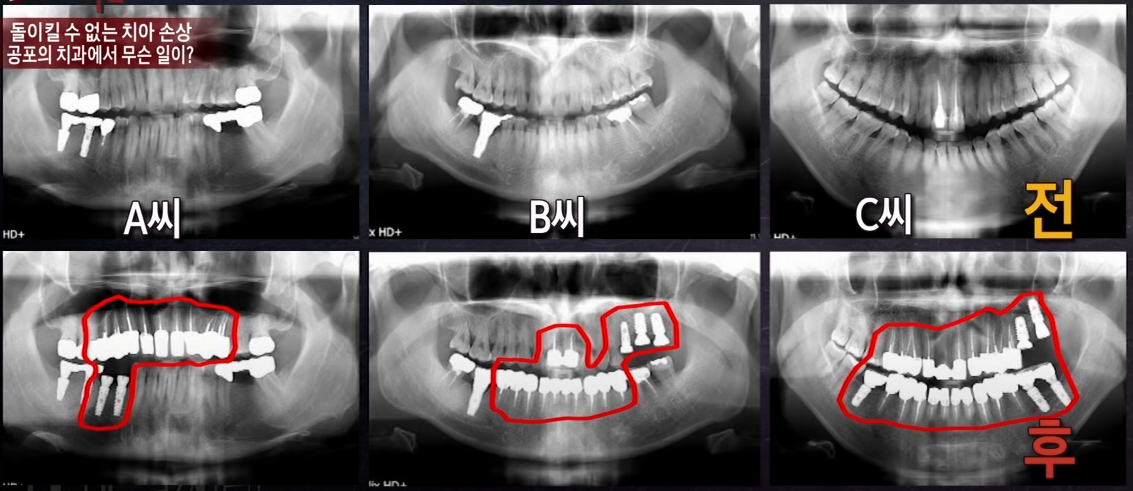

2019년 8월 22일 ‘KBS 제보자들’에서 한 공포의 치과에서

피해를 받았다는 제보자들의 이야기가 방송됐었죠.

피해자들은 매우 충격적인 치아 상태를 보여줬어요

치료 후에는 상태는 참혹했죠.

피해자들의 충치 제거는 정말 필요했을까?

전문가는 “충치가 확실하지 않고 충치가 없었다고 보이는데 많이 갈아버렸다.

건강상 환자에게 득이 될 게 없으면 행위 자체로만 보면 상해다

치아를 왜 갈고 씌우는가?

아무런 이유 없이 멀쩡한 치아를 그렇게 하면 다 상해다.”

라고 설명했어요

충치가 없는데도 충치 치료를 했다는 기가 막힌 상황.